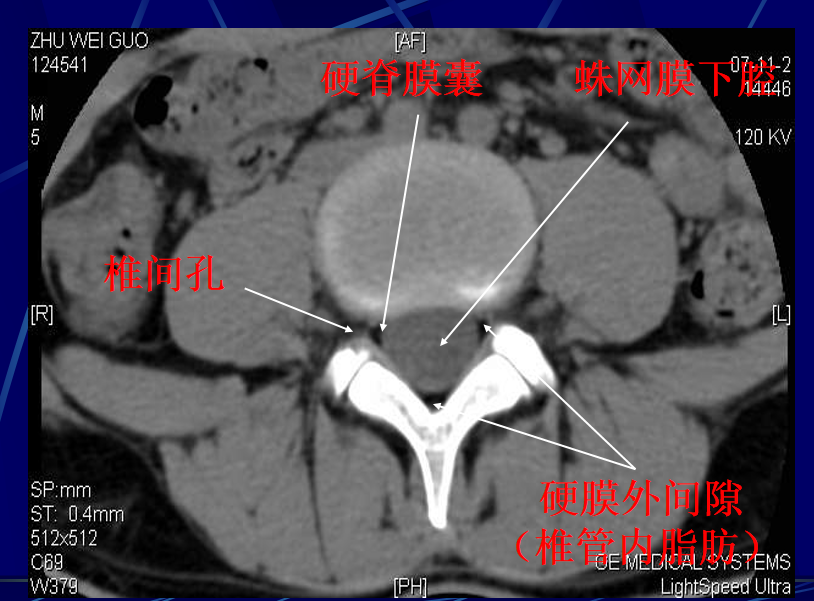

硬脊膜与蛛网膜粘贴在一起,统称为硬脊膜囊硬膜外间隙:骨性椎管与硬脊膜囊之间的间隙内含脂肪密度影蛛网膜下腔:蛛网膜内侧的间隙

• 马尾神经在蛛网膜下腔呈均匀排列的多个圆点状低密度影,含脊神经根。

• 神经根鞘为直径约1~3mm的圆形影,位于硬脊膜囊前外方侧隐窝内。

椎间孔前为椎体,后为椎小关节,上下为椎弓根,内与侧隐窝相连,有脊神经根通过。

椎间孔前为椎体,后为椎小关节,上下为椎弓根,内与侧隐窝相连,有脊神经根通过。侧隐窝:向下外续于椎间孔,有脊神经经过

• 前壁为椎体后外缘

• 后壁为上关节突前面与黄韧带

• 外界为椎弓根

正常前后径为3-5mm,<3 mm侧隐窝狭窄>5mm,肯定不狭窄